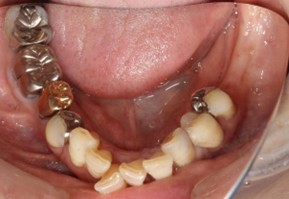

70代 女性

治療前

- 70代/女性

- 患者の具体的な症状

- 下顎の奥歯が義歯で噛みづらいため、インプラント治療を希望

- コーンビームCT、レントゲン撮影

- 診断結果

- 左下6欠損

- 治療詳細

- 左下6インプラント埋入1本、骨造成なし、局所麻酔

- 通院回数

- 8回

- 治療期間

- 6か月